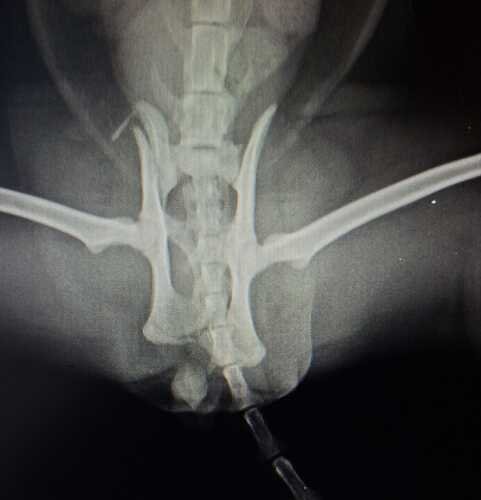

No dia 20/11/25, aconteceu o imprevisto: o Akira foi atropelado e levado imediatamente a uma clínica 24h. No dia 21/11/25, o raio-x revelou uma fratura na pelve (asa de íleo direito e terço médio do ísquio), e agora ele precisa de cirurgia ortopédica para se recuperar e voltar a ser o gatinho ativo que conhecemos.